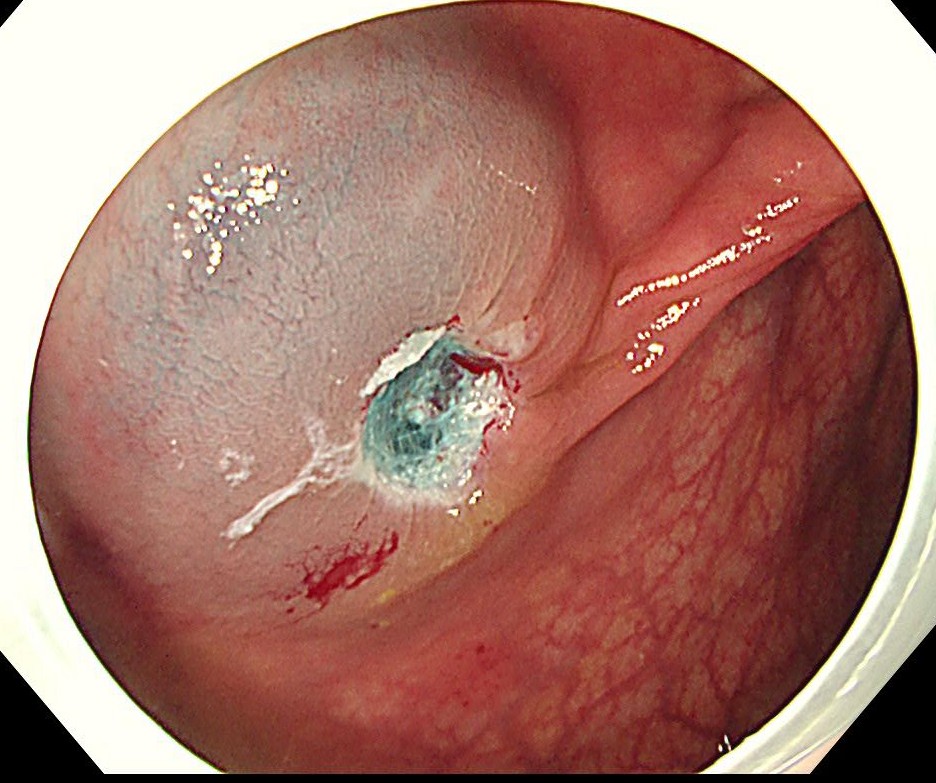

中年女性、下血にて来院。大腸内視鏡をしますと、直腸に15mm大のポリープを認めます。NBI(狭帯域光観察)では構造異形は乏しく、良性ポリープと診断しましたが、下血原因と考え、型のごとく内視鏡切除(EMR)しました。

病理診断にて直腸のSSA/P (sessile serrated adenoma/polyp 鋸歯状腺腫) と診断されました。大腸の鋸歯状腺腫はよくみられる病変ですが、右側結腸に多く、直腸は過形成性ポリープがほとんどで、直腸SSL (鋸歯状病変)は比較的まれです。またその多くが平坦な病変であるため、上記のようなⅠ型のポリープ形状は珍しい病変と思われます。最近の研究結果で直腸の隆起型のSSA/Pはがん化率が高いとする報告も散見され、注意を要する病変と思われます。